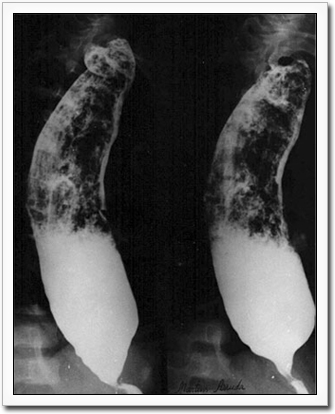

The effects on the esophagus range from asymptomatic motility disorders through mild achalasia to severe megaesophagus.

Megaesophagus in Chagas patient. Photo courtesy of Dr. Anis Rassi Jr.